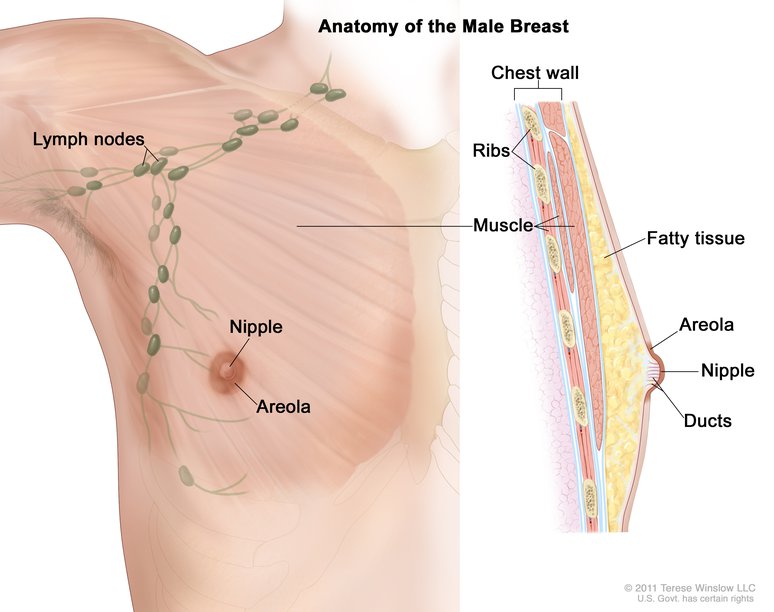

1. Male Breast Cancer (Male Breast Neoplasm)

- Number of People Afflicted Yearly: less than 1% of all breast cancer cases (about 2,550 in the U.S.)

- Area of Body Affected: Male breast tissue

- Is it Treatable?: Yes

- Survival Rate: 5-year survival rate is 84%

Although it is widely known that breast cancer is a tragically common condition among women, many people are unaware that men can also develop breast cancer.

This is due to the fact that breast cancer in males is extremely uncommon and accounts for a fraction of one percent or less of all breast cancer occurrences. It is anticipated that approximately 2,550 men will be diagnosed with breast cancer in the United States in the year 2018.

Although technically speaking males do not have breasts, they do have breast tissue, which is where the cancer can develop.

In contrast to breast cancer in women, which can manifest itself at any point in a woman’s life, male breast cancer almost always manifests in older males. The median age of men when they are first diagnosed with breast cancer is 68 years old.

If detected at an early enough stage, male breast cancer, similar to breast cancer in females, is curable. The five-year survival rate for women diagnosed with breast cancer is approximately 84%, which is also a reasonably high percentage.